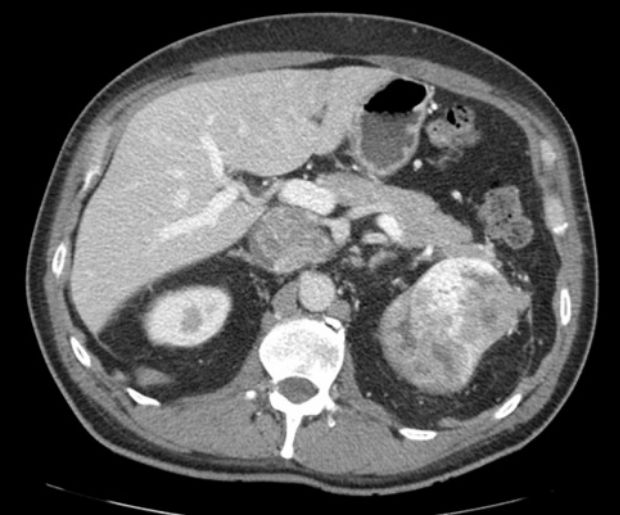

Muž 45 let – potíže s mikcí

Jste lékař urolog a přichází k vám pacient odeslán od praktického lékaře (PL). PL k Vám odesílá muže ve věku 45 let, pro nespecifické mikční potíže, které se objevily po prochlazení. Krev v moči pacient nepozoroval, lékařem to však nebylo došetřeno. Pacient nebyl doposud urologicky sledován, neléčil se.